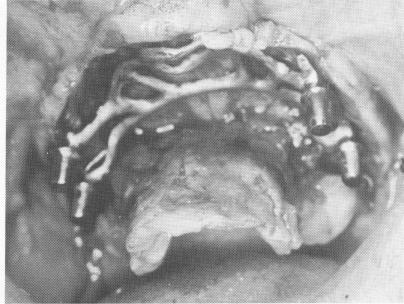

Fig. 11-180. The implant being inserted.

Fig. 11-181. The implant tapped into position.